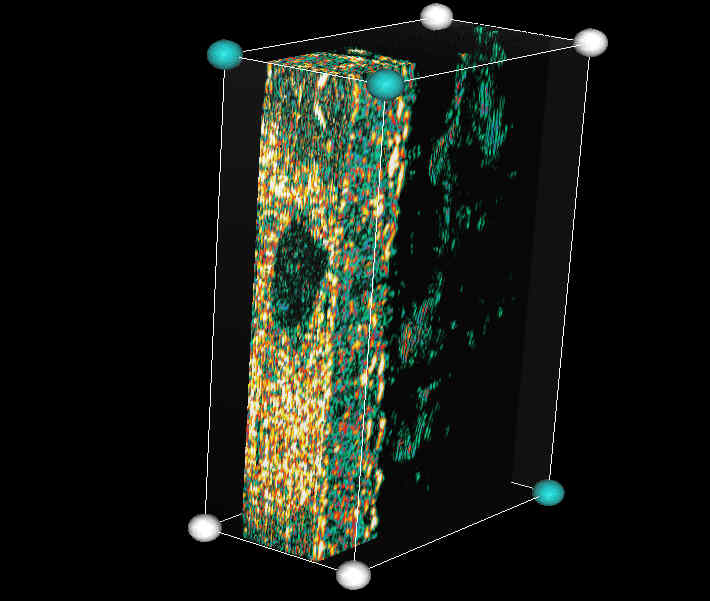

20 MHz 3D images

| Misc. |  Cellulite, arm |

Microdialysis tube |

Intradermal nevus |

Highlight. intrad. nevus |

| Misc. |  Ageband, forearm |

Nevus, skin parallel cut |

Normal, overlying hairs |